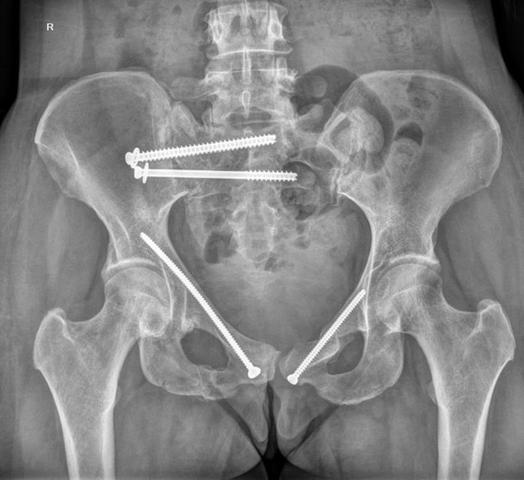

Bei einem vollständigen oder instabilen Beckenbruch ist in den meisten Fällen eine Operation notwendig. Dabei werden die unterbrochenen Beckenteile miteinander verschraubt, um eine stabile Heilung zu ermöglichen. Nach dem Eingriff müssen die Patienten für einige Wochen das Bett hüten. Bei komplizierten oder mehrfachen Beckenbrüchen kann es unter Umständen Monate dauern, bis der Patient seine Beine wieder belasten darf. Die genaue Verweildauer im Krankenhaus richtet sich nach der Schwere der Verletzung und kann mehrere Wochen betragen.